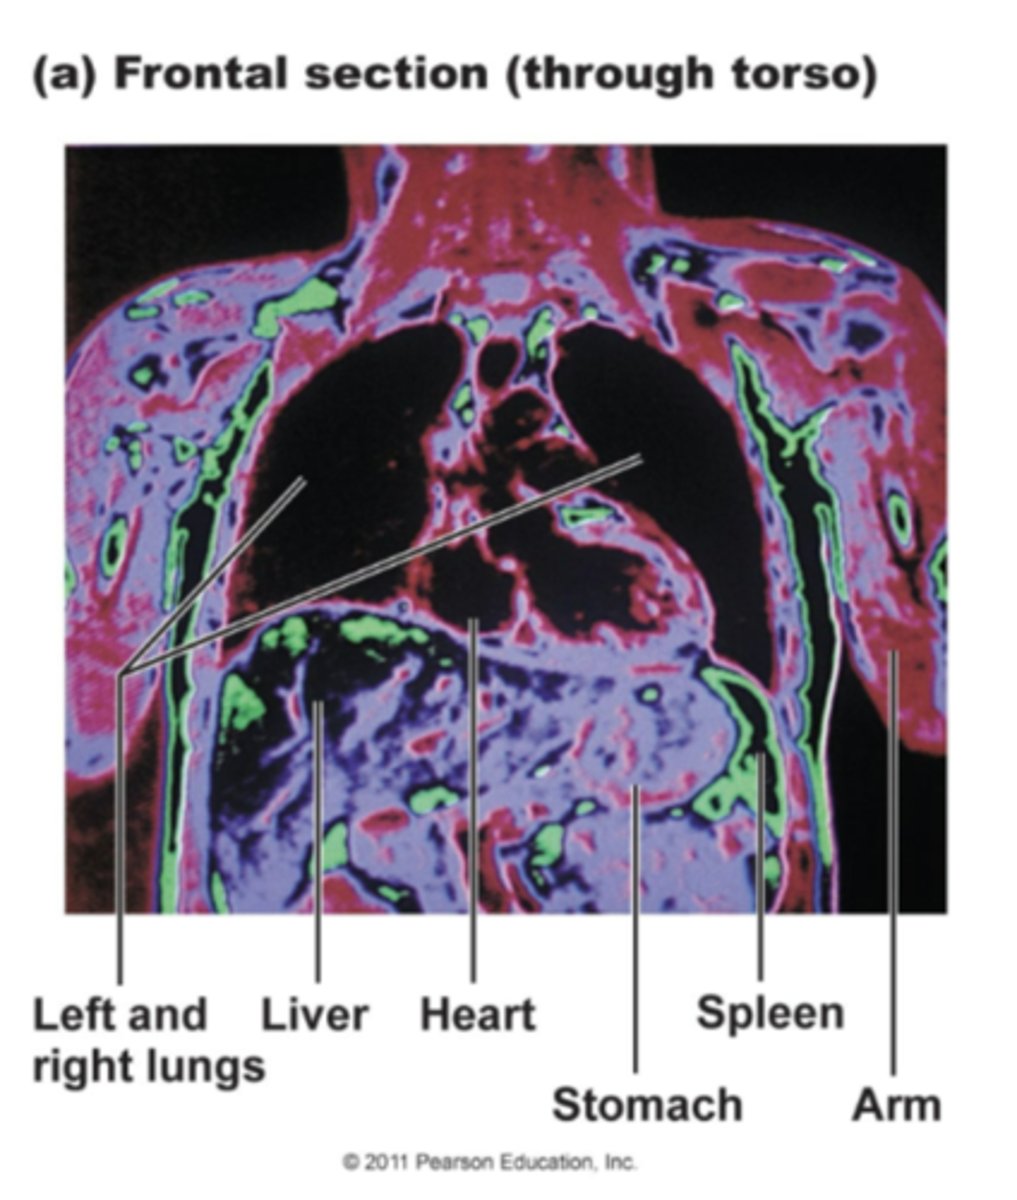

Coronal Section

Also called a 'Frontal' section, this body plane is capable of revealing a wide area. This image is taken of the thorax, and is cut parallel to both shoulder blades(scapulae).